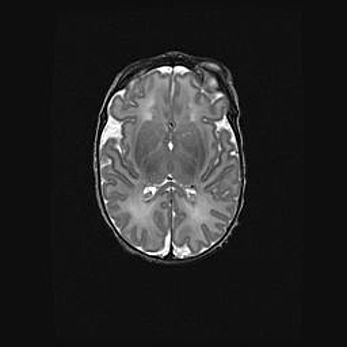

Наружная гидроцефалия с возможной атрофией височных областей.

Возраст: 28 дней

Вес: 3670 г

Пол: мужской

Окружность головы: 38 см

Срок гестации: 40 недель

Гидроцефалия головного мозга у новорожденных – это заболевание, которое характеризуется скоплением избыточного количества спинномозговой жидкости в желудочковой системе головного мозга в результате затруднения её перемещения от места выработки к месту поглощения в кровеносную систему или вследствие нарушения абсорбции. При открытой наружной форме гидроцефалии у новорожденных расширяются и переполняются субарахноидные пространства.

При нормотензивных  формах,  которые,  как  правило,  являются  следствием  перенесенных ишемических  повреждений  паренхимы  мозга,  возможно  сочетание микроцефалии  с нормотензивной гидроцефалией. В основе данных изменений лежит атрофия больших полушарий с преимущественной  локализацией  в  лобно-височных  областях.